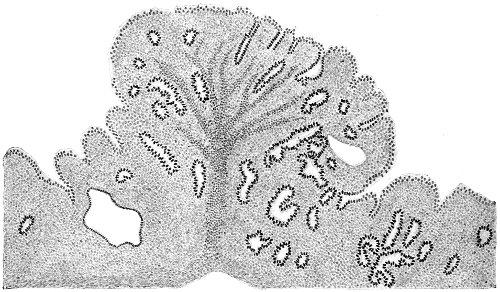

Several varieties of acute vaginitis may be recognized—the simple, the granular, the senile, and the emphysematous. It is unusual to find the entire surface of the vagina involved. The disease is confined to areas or patches separated by healthy tissue.

In simple vaginitis the inflamed membrane remains smooth.

In granular vaginitis, which is the variety usually seen, the papillæ are infiltrated with small cells, and are much enlarged, so that the inflamed surface has a granular appearance.

Senile vaginitis is due to infection of portions of the vaginal mucous membrane that have lost their epithelium as a result of the atrophic changes of old age. This disease occurs in patches of various size, sometimes presenting the character of ecchymosis; in other cases the 50 patches have altogether lost the epithelium, and permanent adhesions may take place between areas which are brought in contact. This form of vaginitis has also been called adhesive vaginitis. It is said that a similar condition may occur in children.

The emphysematous form of vaginitis occurs in pregnancy. The vaginal walls are swollen and crepitating. The gas is contained in the meshes of the connective tissue.

Acute vaginitis is accompanied by dull pain and a sense of fulness in the pelvis. The discomfort is increased by standing, walking, defecation, and urination. There is a free discharge of serum or pus, which may be tinged with blood. The character of the discharge depends upon the variety and the period of the disease. Inspection, which can best be made through the Sims speculum, with the woman in the Sims or knee-chest position, shows the characteristic lesions of inflammation of the mucous membrane.

Acute vaginitis, if neglected, may pass into the chronic form. It usually lingers in the upper part of the vagina, in the fornices, especially in vaginitis of gonorrheal origin. By careful inspection we find here one or more granular patches of inflammation, which cause a vaginal discharge from which man may be infected, and from which infection of the upper portion of the genital tract, the uterus, and the Fallopian tubes may be derived.